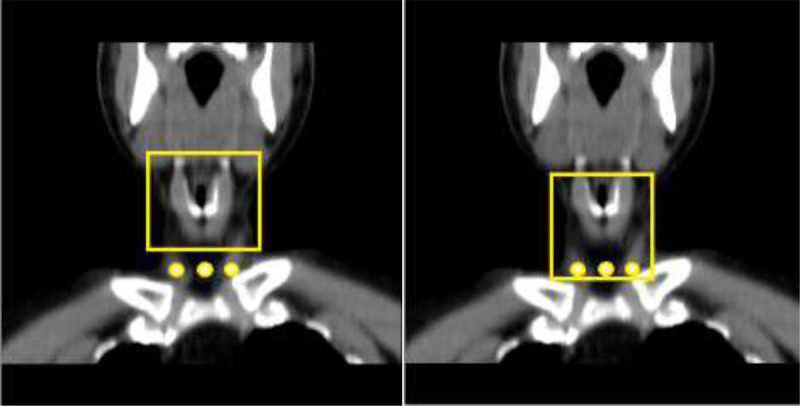

Material and methods: In this computational simulation study, the BEAMnrc Monte Carlo code was employed to model an OPG machine, using 700 million particles across the energy range of 60-75 keV, which is standard for OPG procedures. The Monte Carlo (MC) model was cross-verified by comparing the derived spectra with those in the IPEM Report 78. A head and neck phantom was constructed using CT scan images with a slice thickness of 5 mm. This phantom underwent simulated beam exposure under two conditions: pre-swallow and post-swallow. Subsequently, the percentage depth dose was measured and contrasted across different depths.